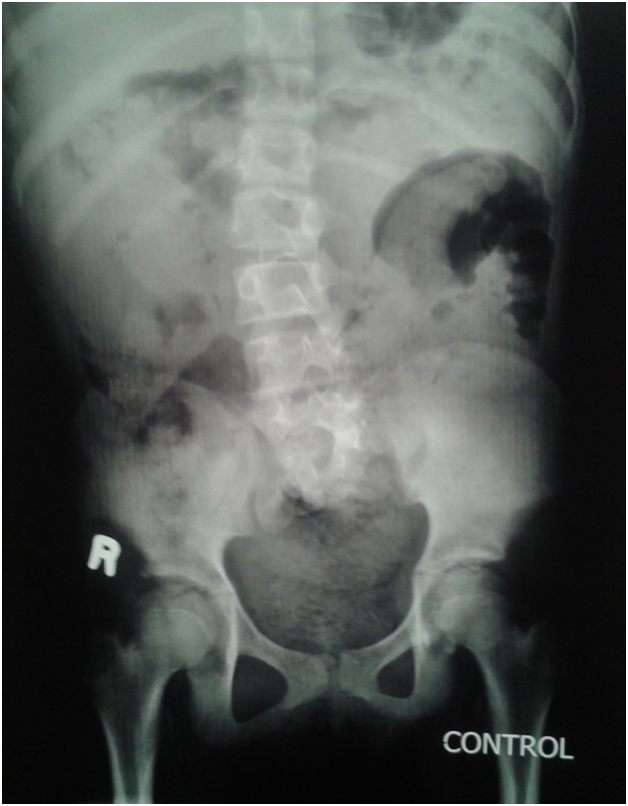

An eleven year old girl was presented to with chronic constipation, persistent dribbling of urine and recurrent urinary tract infections since early childhood. She received treatment by local physicians but remained without proper response. On examination, child was a febrile and her bladder was palpable. Her buttocks were flattened (Figure 1) and external genitalia were wet and excoriated. Anal tone was found decreased on digital rectal examination and the rectum was loaded with hard stool. No definite neurological deficit was found. She was catheterised and stool evacuated with per rectal enema. Her blood analysis showed low haemoglobin (8.1gm %), leucocytosis and raised serum creatinine level (2.2mg %). Urine analysis showed plenty of pus cells and growth of E. coli. Ultrasonography suggested bilateral hydro uretoronephrosis (rt>>lt) with loss of cortico medullary differentiation on right kidney and thickened irregular bladder with significant post void residual urine. Tc-99m DTPA renogram shows poorly functioning right kidney and satisfactorily functioning left kidney. Complete sacral agenesis, 5th lumbar vertebral atrophy and scoliosis with convexity towards right side seen in the control film (Figure 2) while neurogenic bladder with bilateral grade V vesico- ureteric reflux revealed on Voiding phase cystourethrogram (Figure 3). Child was further evaluated with urodynamic study, which suggested an overactive bladder in filling phase (Figure 4). Repeat blood analysis shows (Figure 4) normalisation of serum creatinine (1.2mg %). Her catheter has been removed and she has been placed on self clean intermittent catheterisation along with anti cholinergic (oxy butinine 5mg/daily) and laxative.

Figure 2 Complete Sacral agenesis, 5th lumbar vertebral atrophy.

Figure 3 Complete Sacral agenesis, 5th lumbar vertebral atrophy